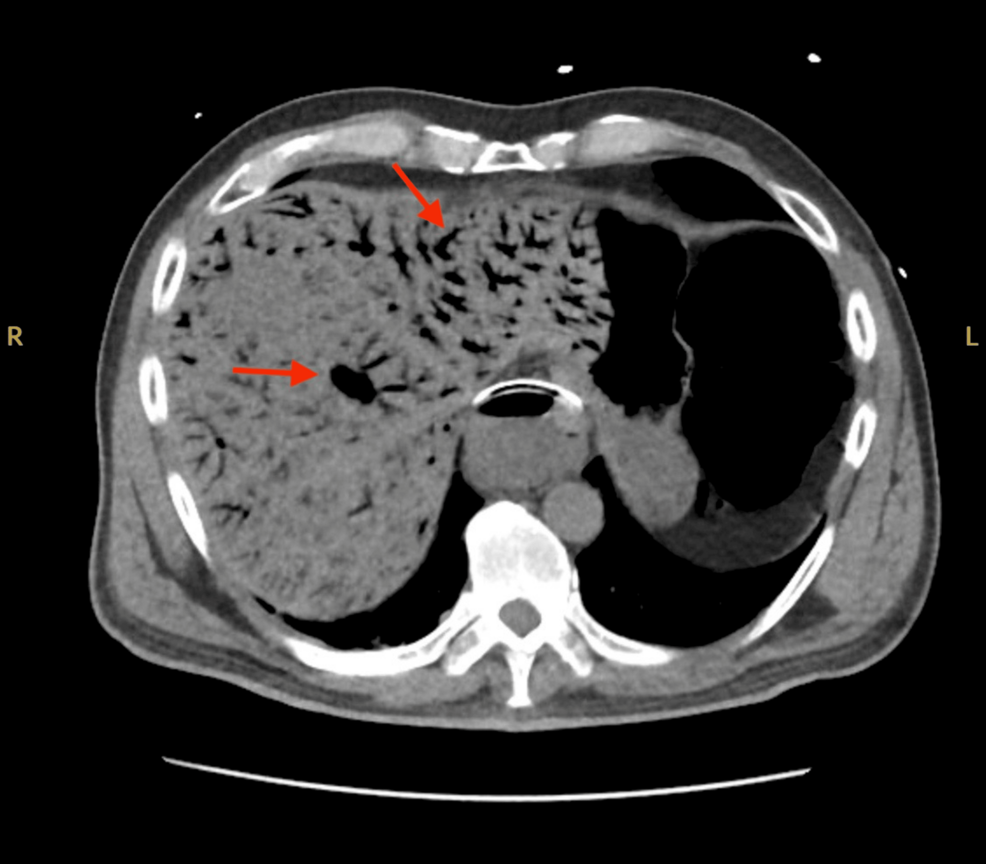

A 76-year-old woman with a history of hypertension and type 2 diabetes mellitus is brought to the emergency department 60 minutes after the acute onset of left-sided abdominal pain and nausea with vomiting. Three weeks ago, she underwent emergency surgical revascularization for acute left lower extremity ischemia. Physical examination shows left upper quadrant tenderness without rebound or guarding. Serum studies show an elevated lactate dehydrogenase level. Laboratory studies, including a complete blood count, basic metabolic panel, and hepatic panel, are otherwise unremarkable. A transverse section of a CT scan of the abdomen is shown. Further evaluation is most likely to show which of the following?